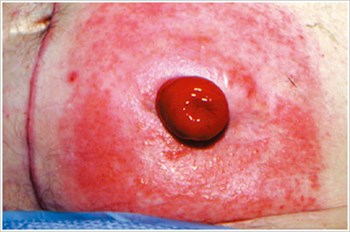

Pyoderma Gangrenosum

Description/Causes:

An inflammatory skin disease often seen in patients with inflammatory bowel disease ( IBD ) such as Crohn's disease or ulcerative colitis.

Symptoms:

- Irregularly shaped, red, painful, infected ulcers, with red-to-purple rolled margins; appear on legs, buttocks, face, and peristomal area.